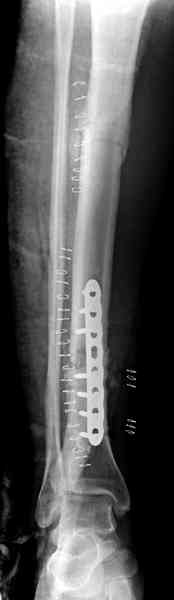

Недавно на нашей ежемесячной Morbidity&Mortality

conference мы разбирали похожий случай, ложный сустав большеберцовой кости после резекции опухоли.

К нашему онкологу-ортопеду обратился больной с жалобами на боли в голени, из рассказа - год назад была сделана биопсия большеберцовой кости, но название заболевания "не запомнил”.

Оперирован в военном госпитале с заменой сегмента

аллокостью большеберцовой кости и после демобилизации явился для постоянного наблюдения по месту жительства.

В литературе "A Classic Adamantinoma Arising from

Osteofibrous Displasialike Adamantinoma in the Lower Leg: A case report and Review of the Literature похожие снимки.

Наши имели проблему со сращением, пришлось им сделать динамизацию, дополнительную аутопластику.

Снимки представлены.